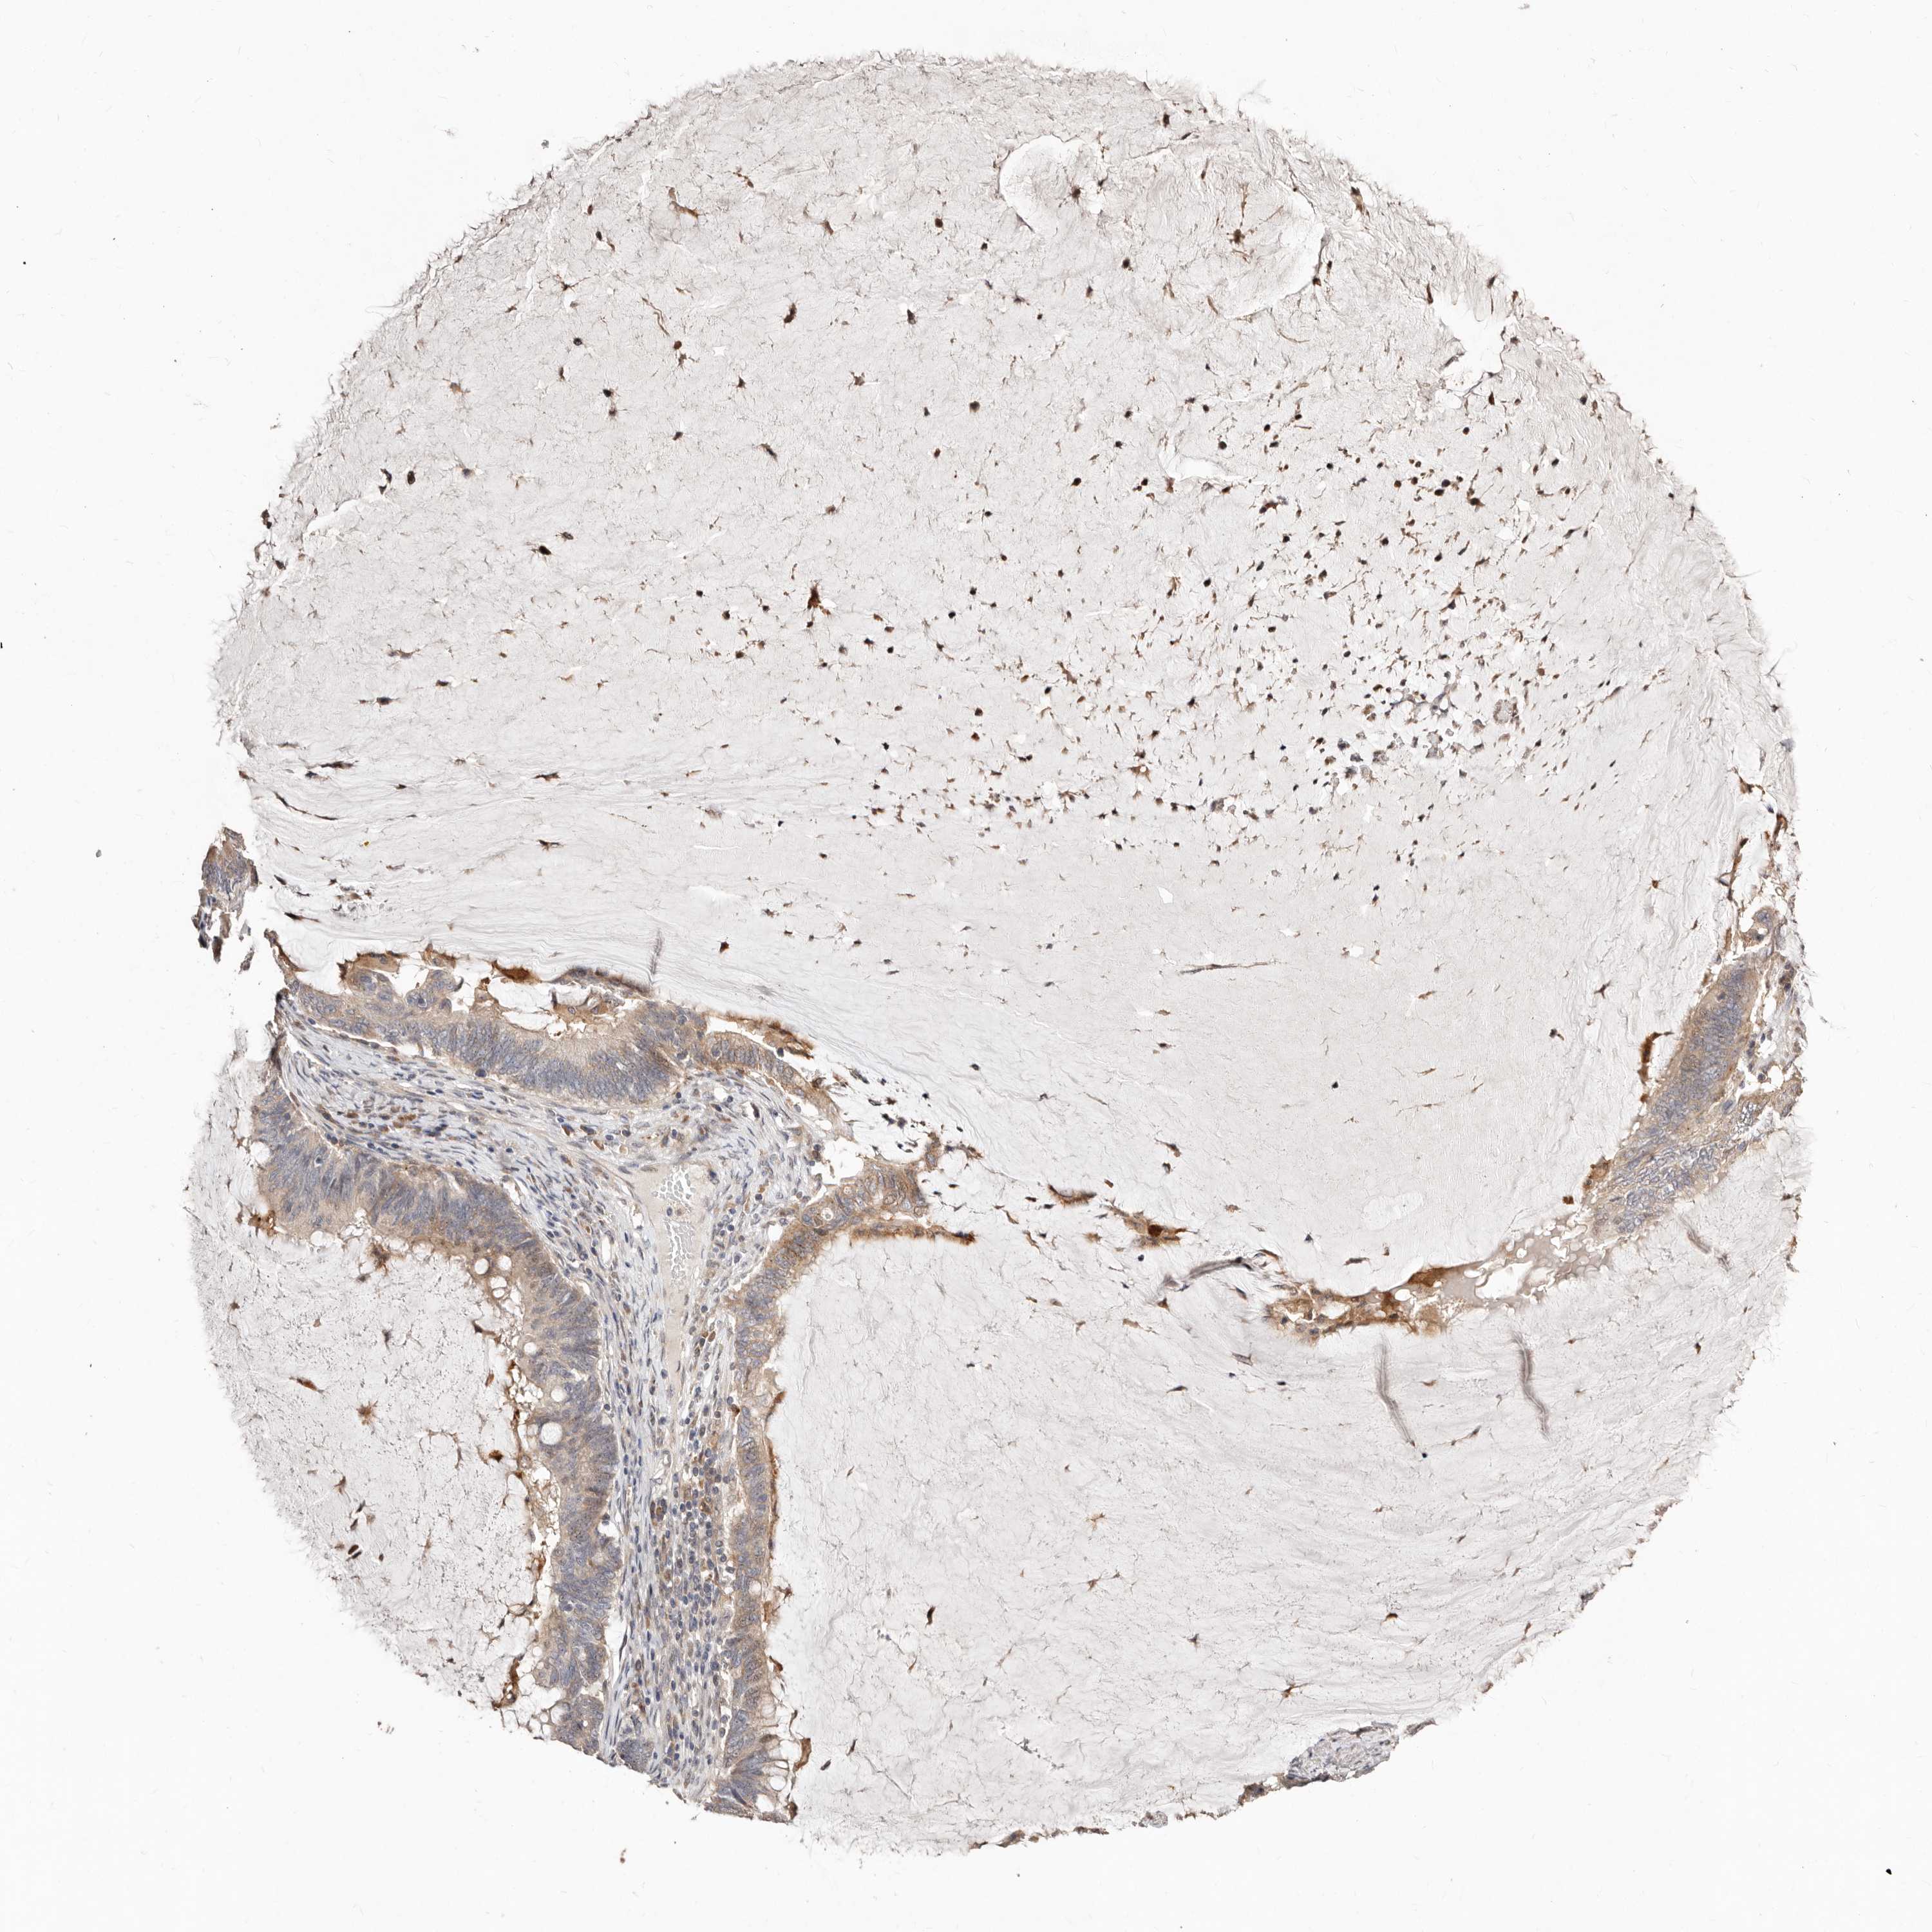

OVARIAN CANCER - Protein expressioni

A mouse-over function shows sample information and annotation data. Click on an image to view it in a full screen mode. Samples can be filtered based on level of antibody staining by selecting one or several of the following categories: high, medium, low and not detected. The assay and annotation is described here.

Note that samples used for immunohistochemistry by the Human Protein Atlas do not correspond to samples in the TCGA dataset.

Antibody stainingi

Antibody staining in the annotated cell types in the current human tissue is reported as not detected, low, medium, or high, based on conventional immunohistochemistry profiling in selected tissues. This score is based on the combination of the staining intensity and fraction of stained cells.

Each image is clickable and will lead to virtual microscopy that enables deeper exploration of all samples and also displays staining intensity scores, fraction scores and subcellular localization as well as patient and tissue information for each sample.

Antibody HPA029165

Antibody HPA029167

Antibody CAB028574

Cystadenocarcinoma, serous, NOS

Carcinoma, endometroid

Cystadenocarcinoma, mucinous, NOS

Carcinoma, NOS